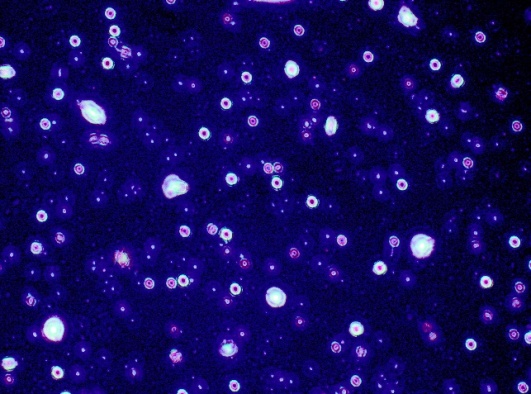

Optical micrograph

A thin layer of a formed colloidal dispersion of loaded RS-CSNPs were spread on a slide, diluted with a small drop of deionized water then dried. The nature of nanoparticles was observed and the presences of drug-loaded nanoparticles, which are insoluble, were focused under the light microscope (Olympus-CKX 41 SF, Philippines) at high magnification powers (10×and40×). Photomicrographs were taken using Fujifilm Finepix F 40 fd (8.3 MP) digital camera with 3 × optical zoom [20].

Morphology of Rivastigmine loaded optimal formula by optical and electron microscopy

Fig. 3 shows the morphology of nanoparticles by optical microscopy, the particles are smooth circular, encapsulating drug in the core and all particles are approximately in the same size. Particles surface surrounded with thin layer of non-ionic surfactant tween 80 assure particle stability and enhance uptake by cells. Fig. 4 (A) and (B) show TEM morphology of nanoparticles in aqueous dispersion at 40,000 magnifications, the largest particles were found in drug-loaded CSNPs through range from 31.7 d. nm to 115 d. nm while unloaded CSNPs were smaller in size range from 9.73 d. nm to 50.5 d. nm. Fig. 5 shows SEM the particles appear spherical with a hairy surface.

Fig. 3: Optical view of loaded optimum CSNPs formula (F15)